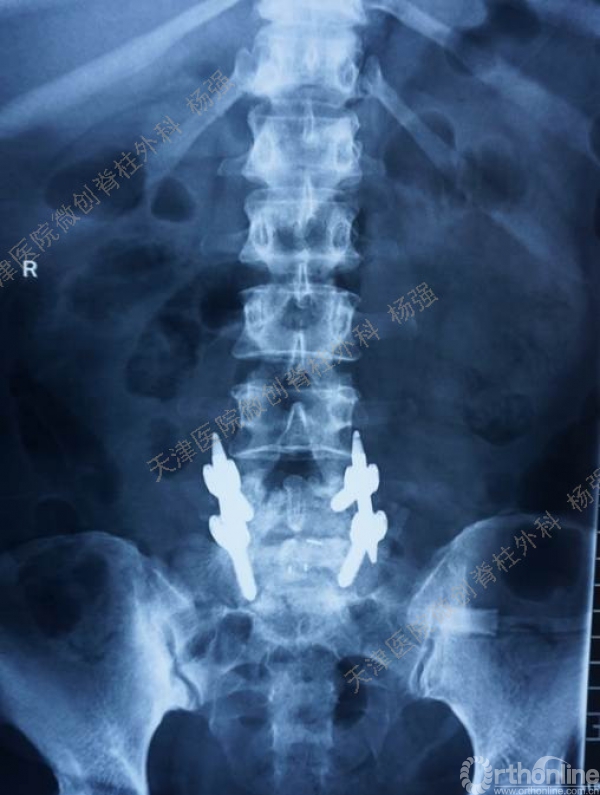

腰5椎体前滑脱I-II°,峡部裂,动力位显示腰5-骶1节段明显失稳

CT、MRI示:腰5椎体前滑脱,腰5/骶1水平间盘突出,腰5双侧椎弓峡部裂